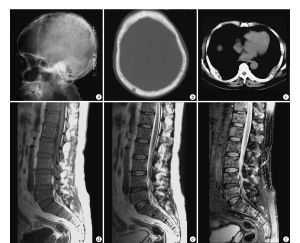

多發性骨髓瘤好發於60歲以上的中老年人,並不是短時間產生臨床症狀的,其病情通常是漸進式的,且症狀不明顯,大部份病人是因疼痛,尤其是下背痛或骨折就醫而被發現。

③X線檢查有溶骨性損害和(或)廣泛骨質疏鬆。

5.骨X線片。CT或同位素掃描:可發現多部位穿鑿樣溶骨性病變或廣泛性骨質疏鬆。